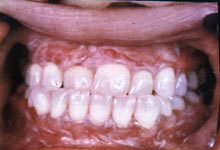

本病好发于40~49岁的女性,患病率为0.5%左右,发病部位多见于颊、舌、唇及牙龈等粘膜, 病变常为对称性分布,尤以颊粘膜最为多见。典型病损是在粘膜上出现白色或灰白色的条纹,条纹之间的粘膜发红,这些条纹可呈网状、线状、环状或树枝状。

2.口腔粘膜损害:

往往有明显的对称性或双侧性。患者有粘膜粗糙感、紧缩感与轻度刺激痛。

3.口腔扁平苔藓的发生部位与临床类型:

1)颊粘膜和前庭沟:是扁平苔藓最常见的部位。

③网状:为细而稠密的白纹,可伴有糜烂。